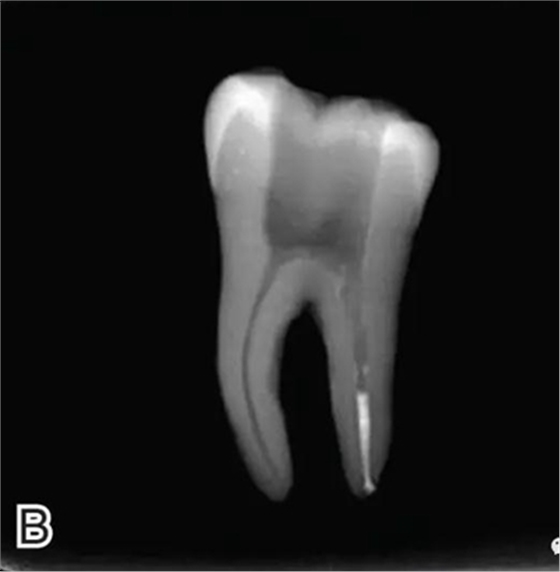

要求工作尖能自由到達(dá)距根尖4~5 mm(有學(xué)者提出3~4 mm)的位置并能輕微接觸根管壁,用橡皮片做好標(biāo)記(圖1)。

圖1 選擇攜熱器工作尖,A.試攜熱器尖 B.工作尖在根內(nèi)的位置